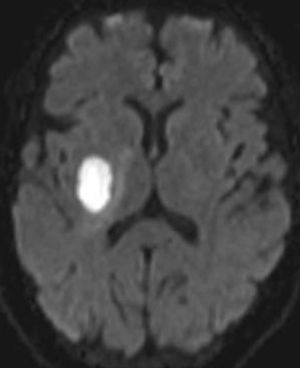

Cerebral abscess

#DWI has proved useful in distinguishing abscesses from necrotic tumors, resolving hematomas and other fluid-filled cavities.